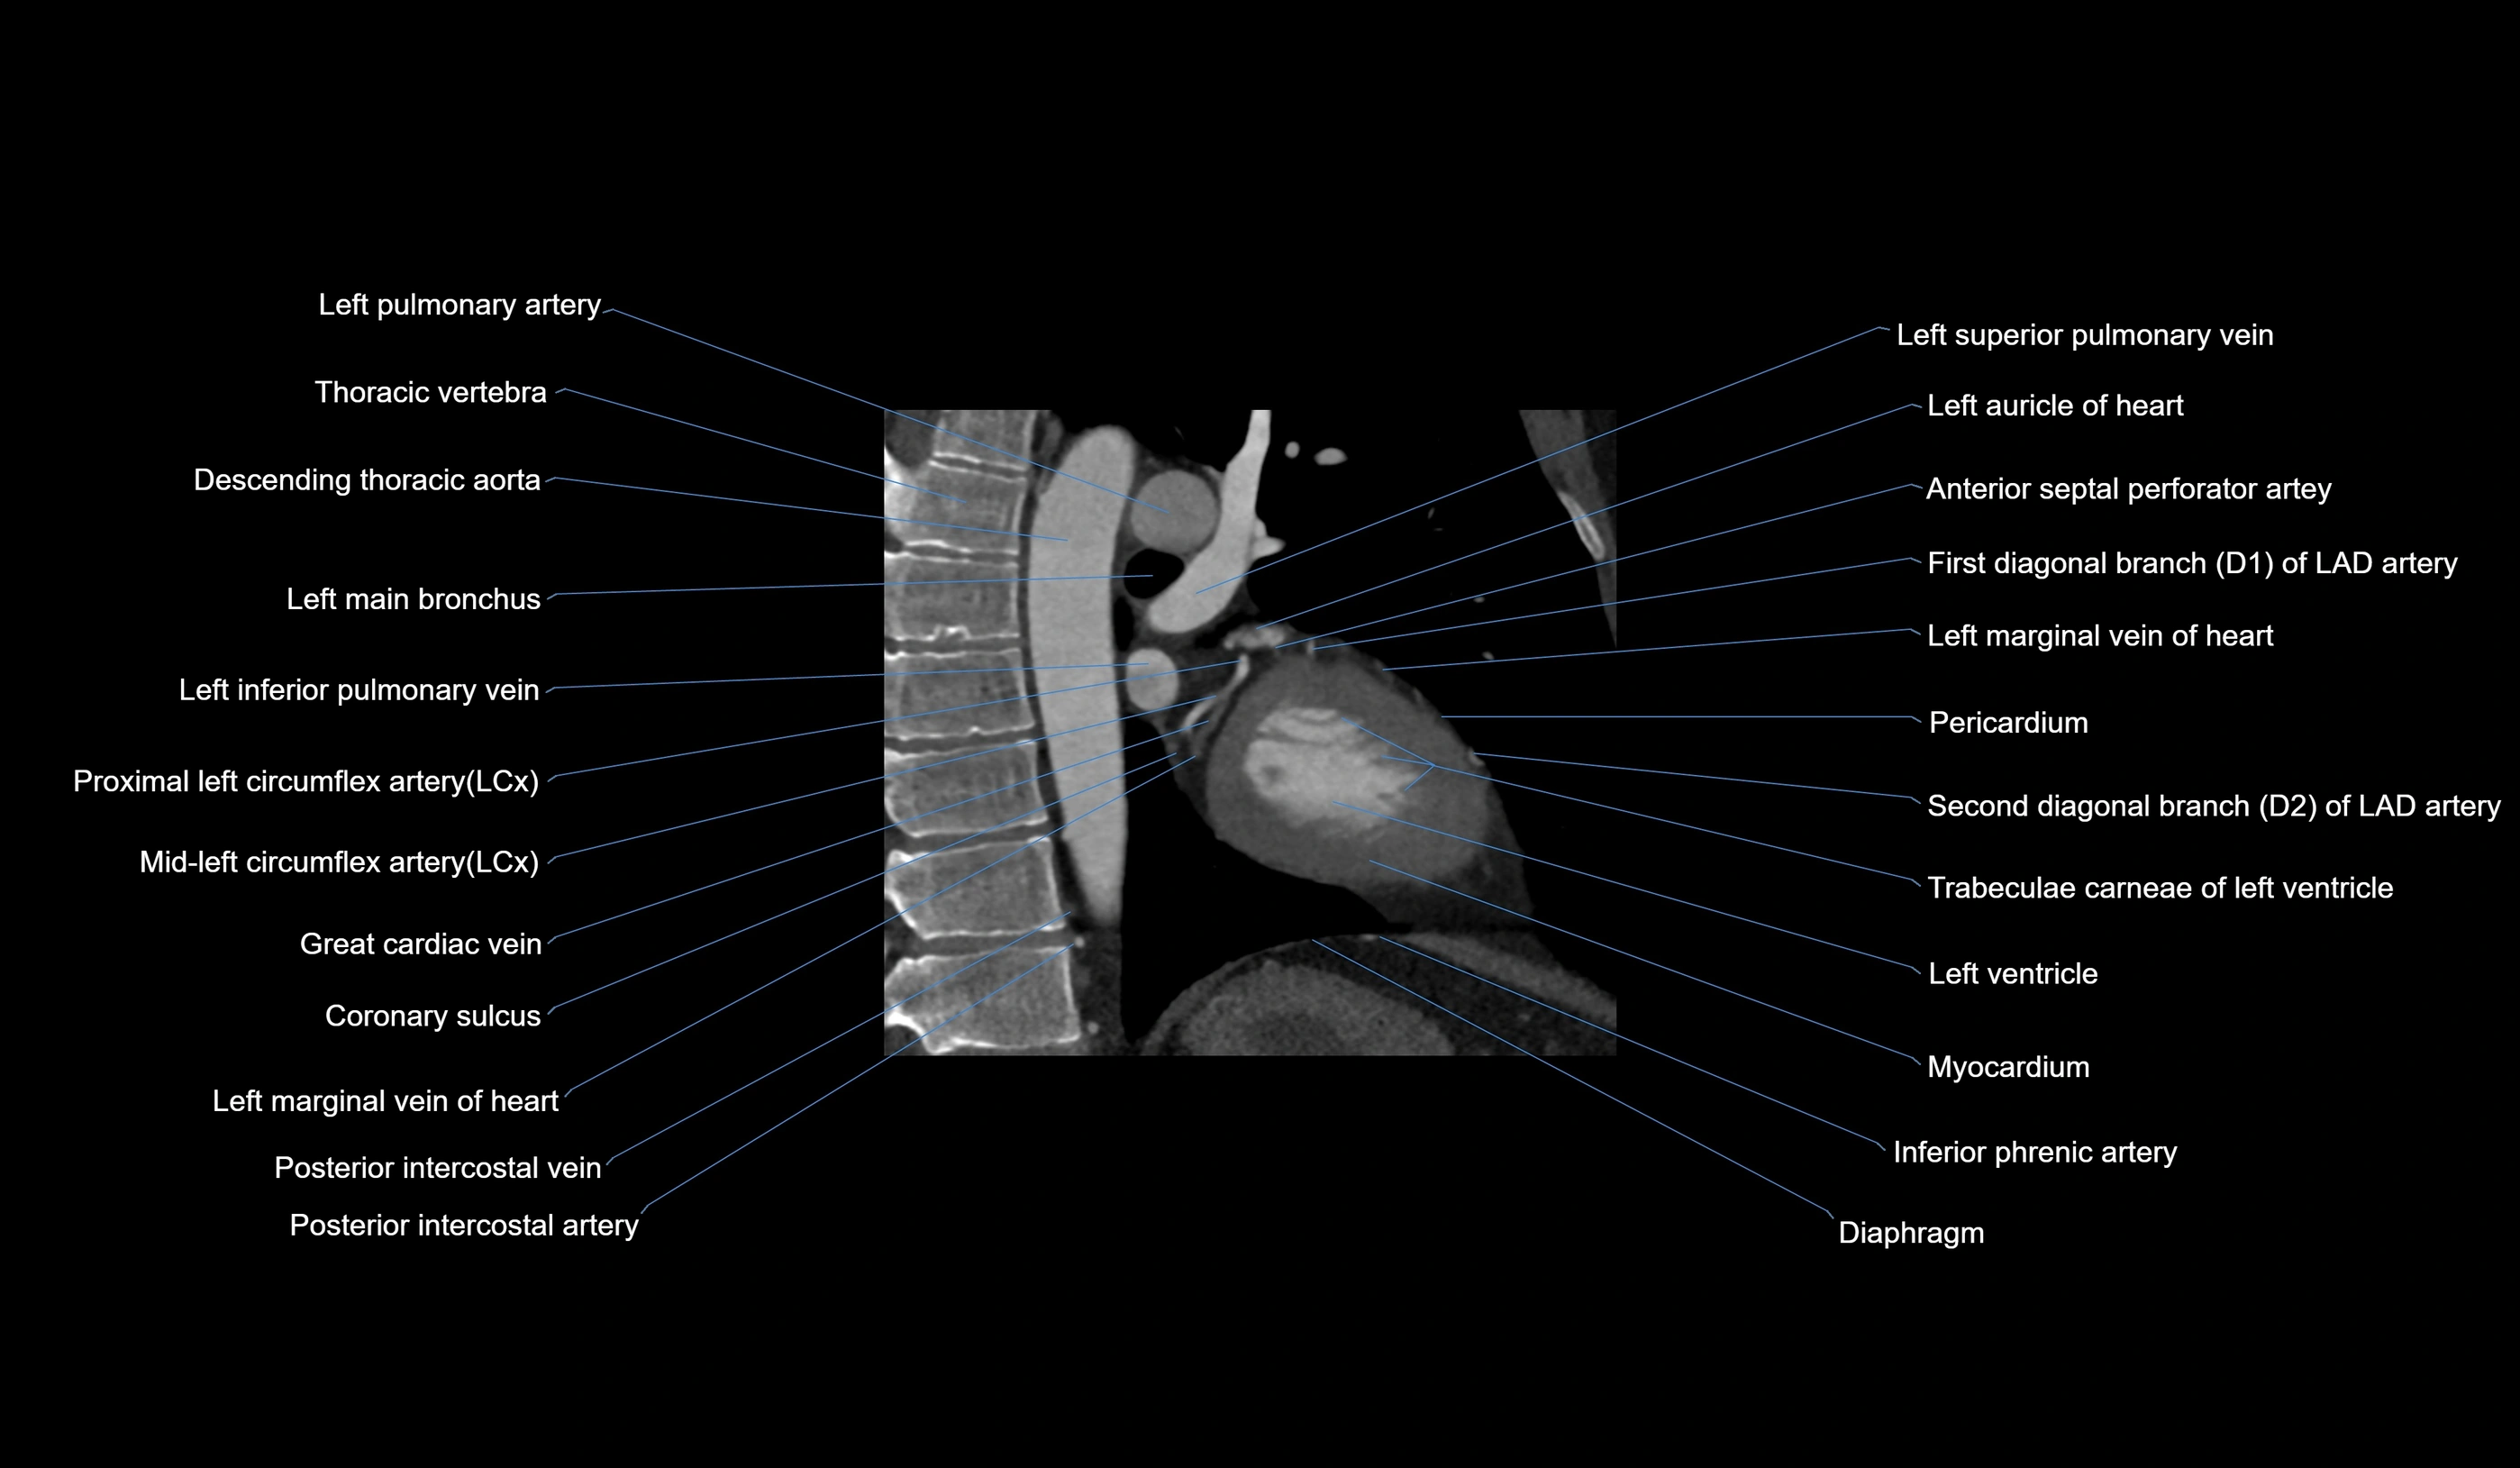

- Left pulmonary artery

- Descending thoracic aorta

- Left main bronchus

- Left inferior pulmonary vein

- Circumflex artery (LCx)

- Great cardiac vein

- Coronary sulcus

- Left marginal vein

- First diagonal branch (D1) of LAD

- Second diagonal branch (D2) of LAD

- Trabeculae carneae

- Left ventricle

- Myocardium

- Inferior phrenic artery

- Diaphragm

- Left superior pulmonary vein

- Left auricle

- Posterior intercostal arteries

- Posterior intercostal veins